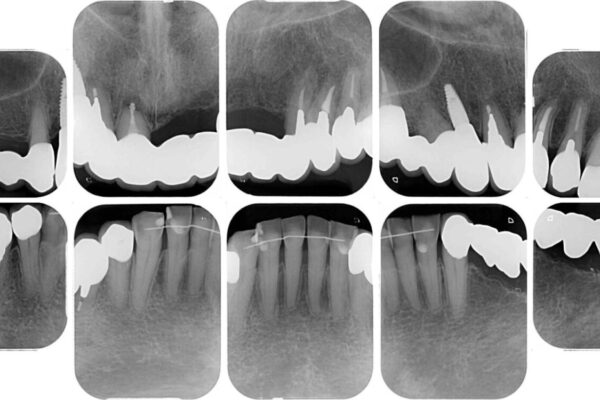

治療前

• 前歯をきれいにしたい インプラントや部分矯正を用いた総合歯科治療 治療前画像